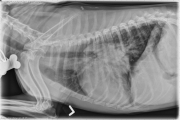

This week’s case is an 11 year old female spayed Jack Russell Terrier, presented for exercise induced cough/syncope with a perihilar mass effect and peribronchial lung pattern. What is your assessment?

R LAT Thorax

There is a mass in the region of the left ventricle of the heart, which is causing lateral deviation of the left caudal bronchus and splaying of the mainstem bronchi. The carina remains in a relatively normal position on the lateral projections, and there is moderate narrowing of the caudal mainstem bronchi. There is a diffuse peribronchial pattern in the lungs, more pronounced on the right cranial and right caudodorsal lung lobes. The pulmonary vasculature is prominent. There is osteoarthrosis of the shoulders and hepatomegaly.

Perihilar mass – left atrium, lymph node

Echocardiography – there was a large (at least 6 x 6 cm), lobulated mass in the left atrium that appeared to be arising from the left atrial lateral wall. It was causing marked left atrial enlargement. The mass did not appear to be arising from the interventricular septum. There was mitral regurgitation present. The left ventricle, right ventricle and right atrium were not enlarged. There was no tricuspid regurgitation, pulmonic or aortic stenosis present.

Assessment and recommendations – This is a large mass in an unusual location. Possible differential diagnosis include myxoma, myxosarcoma, ectopic thyroid carcinoma, fibroma(sarcoma), chondrosarcoma and leiomyosarcoma. There are limited treatment options available for any of these tumors in this location. The most definitive treatment would be attempted surgical removal with histology however this will require open heart surgery with cardiac bypass. The tumor is in a location where obstruction to pulmonary venous inflow may occur. If this occurs, congestive heart failure will result. Hence, owner monitoring of sleeping respiratory rate is advised. The tumor may also induced cardiac arrhythmias. There was no evidence of arrhythmia on physical examination today however, periodic reevaluation, especially if the syncopal episodes worsen is advised. Without surgical removal the prognosis is poor.